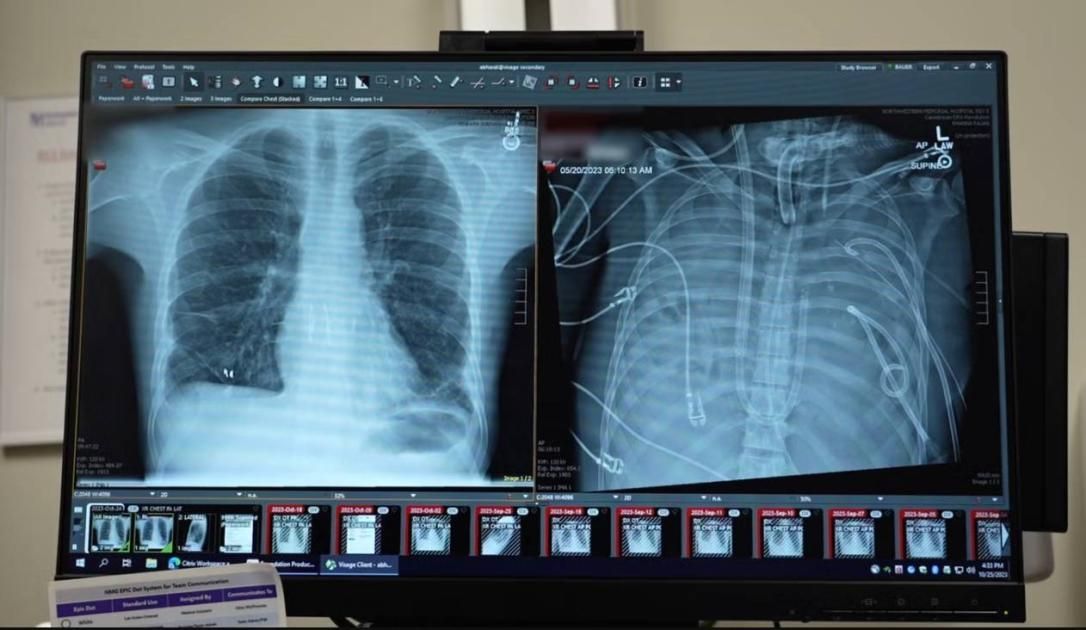

أنقذ جراحون أمريكيون من جامعة نورث وسترن بولاية إلينوي، حياة رجل يبلغ 33 عاماً بعد أن عاش يومين كاملين دون رئتين، باستخدام واحدة اصطناعية مؤقتة قبل إجراء عملية زرع اثنتين مزدوجتين.

أصيب الرجل بمتلازمة الضائقة التنفسية الحادة نتيجة التهاب إنفلونزا، ما تسبب في تدهور رئتيه بسرعة وإصابته بالتهاب رئوي بكتيري حاد، أدى في نهاية المطاف إلى فشل قلبه وكليتيه ورئتيه، وأصبح زرع الرئتين الخيار الوحيد لإنقاذ حياته.

وقال د. أنكيت بهارات، وجراح الصدر في الجامعة: حالة المريض كانت حرجة، وتوقف قلبه فور وصوله إلى المستشفى، ما استدعى إجراء الإنعاش القلبي الرئوي، فعندما يكون الالتهاب شديداً لدرجة أن الرئتين تتضرران بشكل لا يمكن علاجه، يموت المرضى.

وأضاف: كان جسم المريض أضعف من أن يقبل رئتين جديدتين ويحتاج إلى مزيد من الوقت للشفاء من الالتهاب، لذلك صممنا له رئة اصطناعية مؤقتة تقوم بوظائف الأكسجة وإزالة ثاني أكسيد الكربون، والحفاظ على استقرار تدفق الدم عبر الجسم حتى تتوفر رئتا المتبرع.

وتابع: بعد يومين، أصبحت رئتا المتبرع متاحتين وأجريت للمريض عملية زرع رئة مزدوجة بنجاح وعاد إلى حياته اليومية بوظائف رئوية طبيعية.

وأكد أن هذه التجربة تقدم دليلاً على أن بعض مرضى متلازمة الضائقة التنفسية الحادة يحتاجون لزرع رئتين للبقاء على قيد الحياة، وأن استخدام الرئة الاصطناعية يمكن أن يكون حلاً مؤقتاً فعالاً حتى توفر رئتين جديدتين.